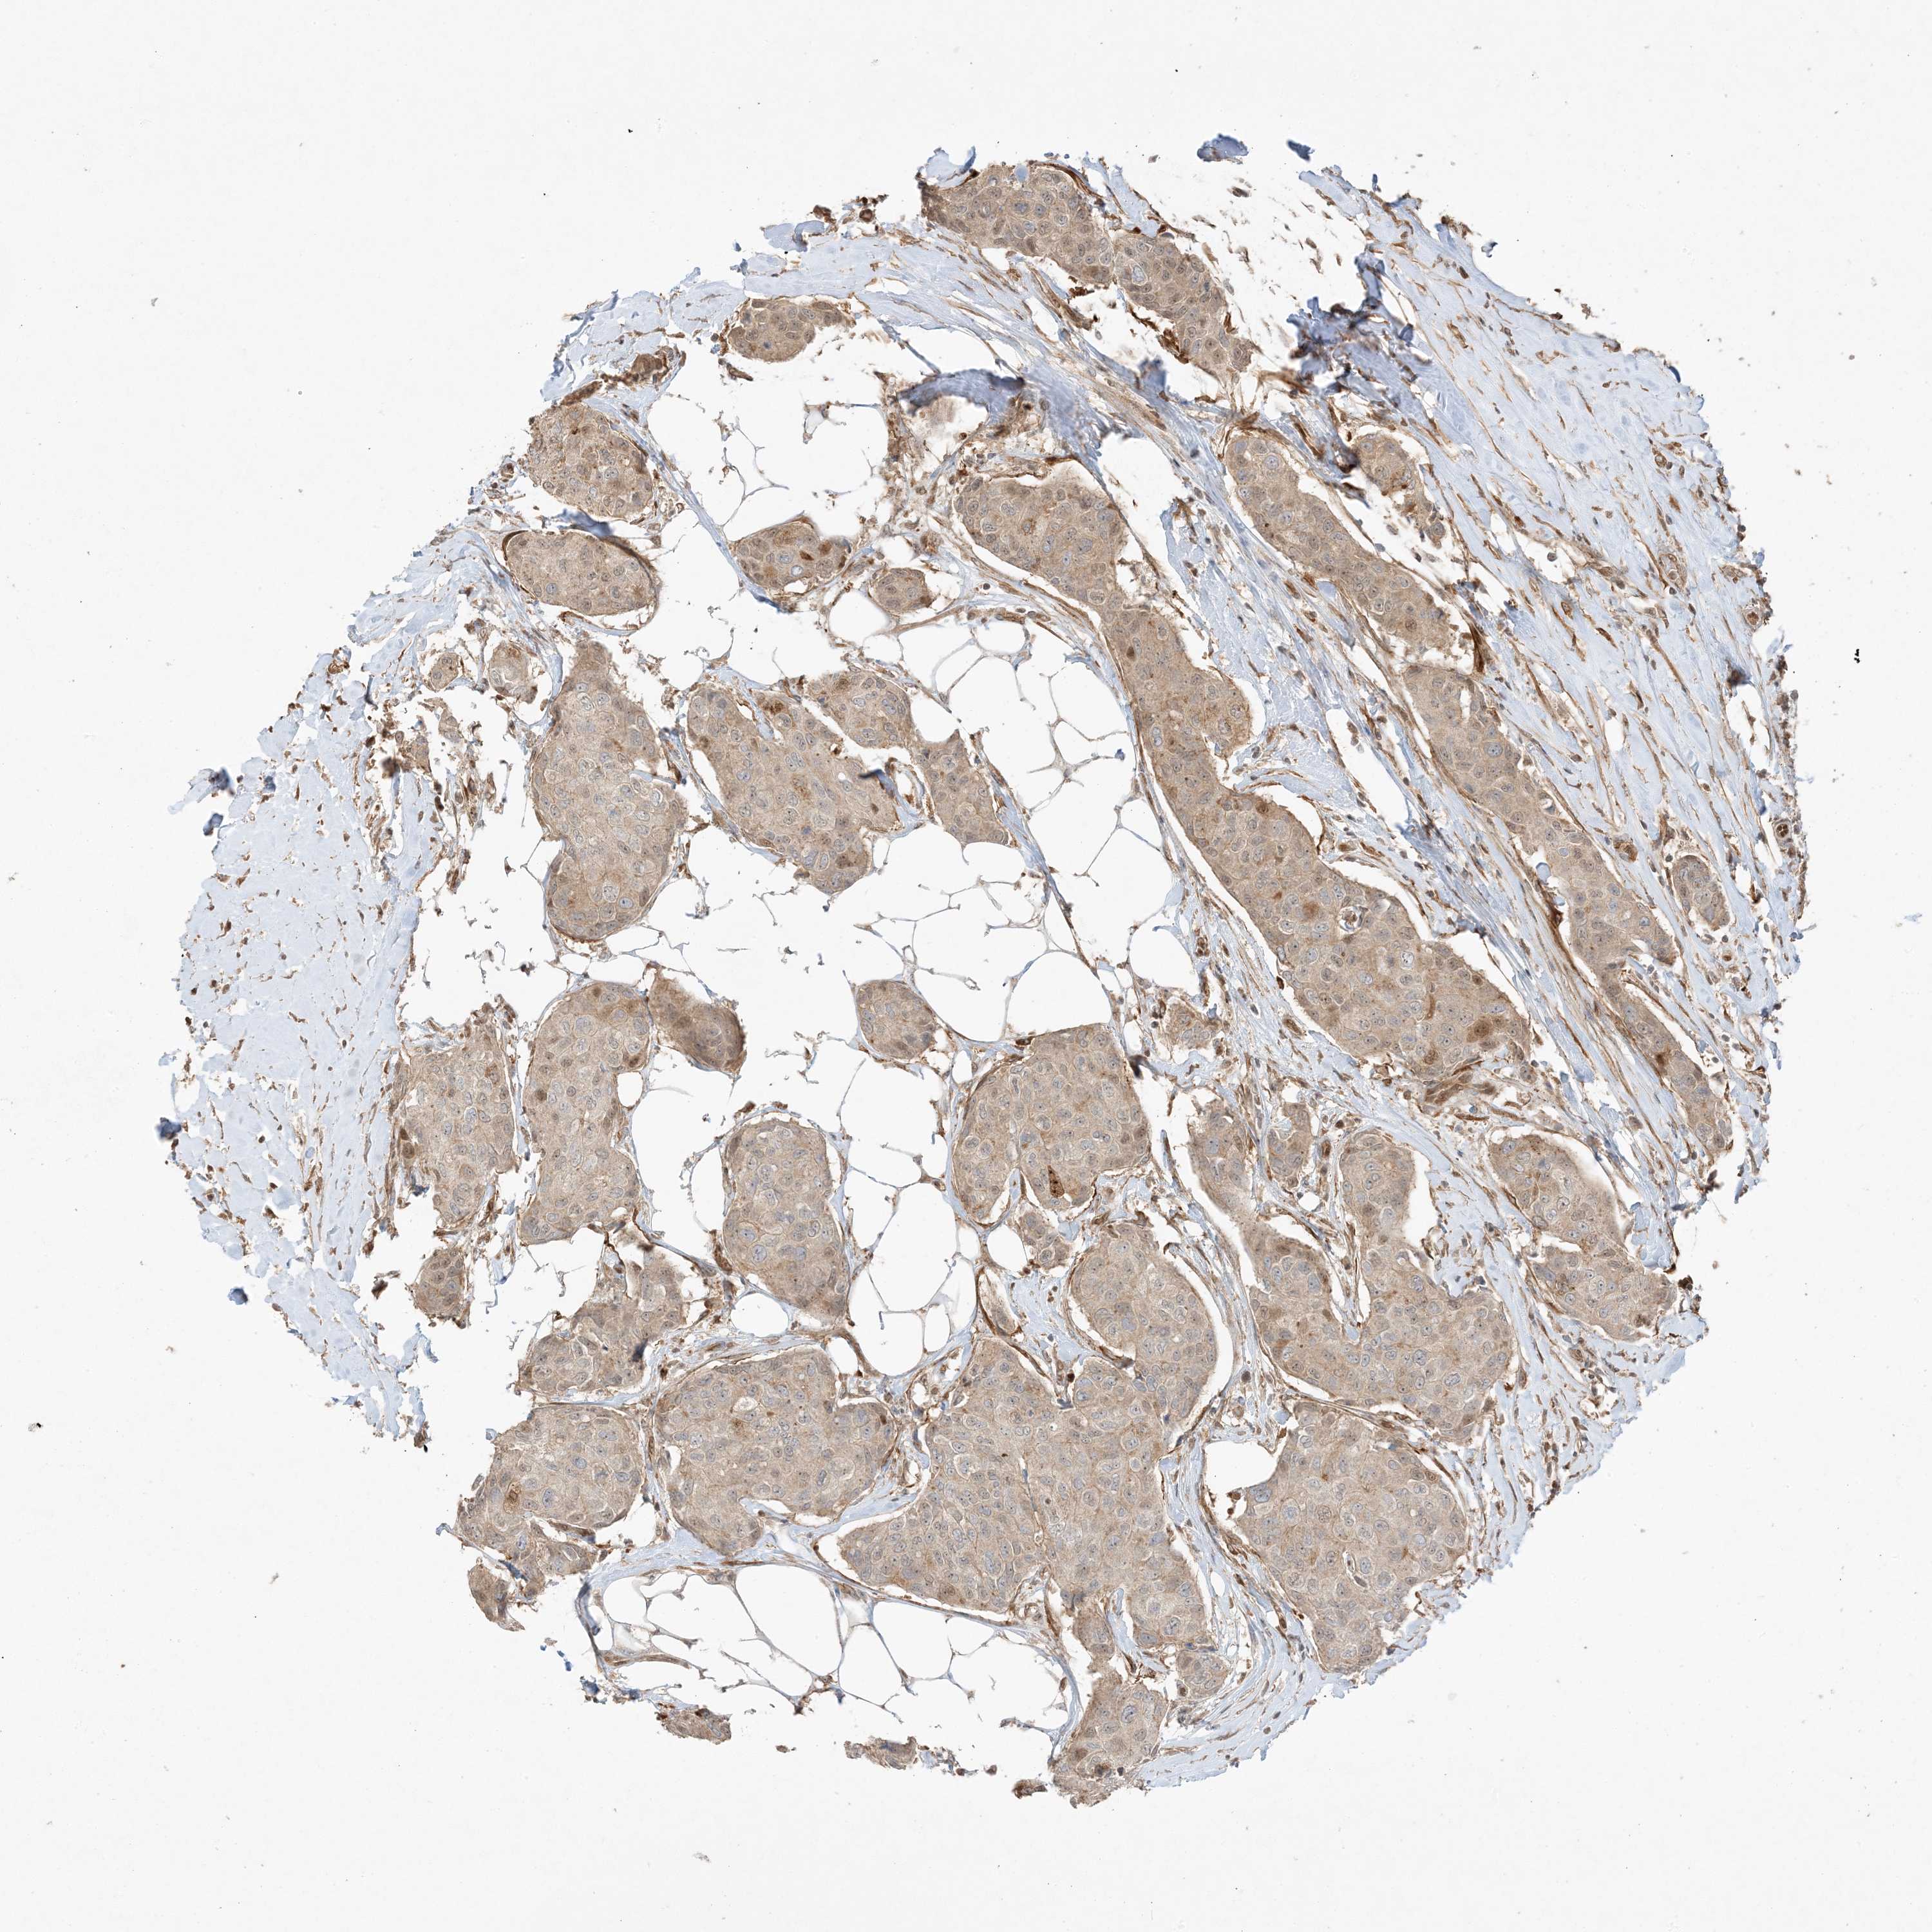

CANCER BREAST CANCER Show tissue menu

BRCA TCGA BRCA VALIDATION PROTEIN EXPRESSION